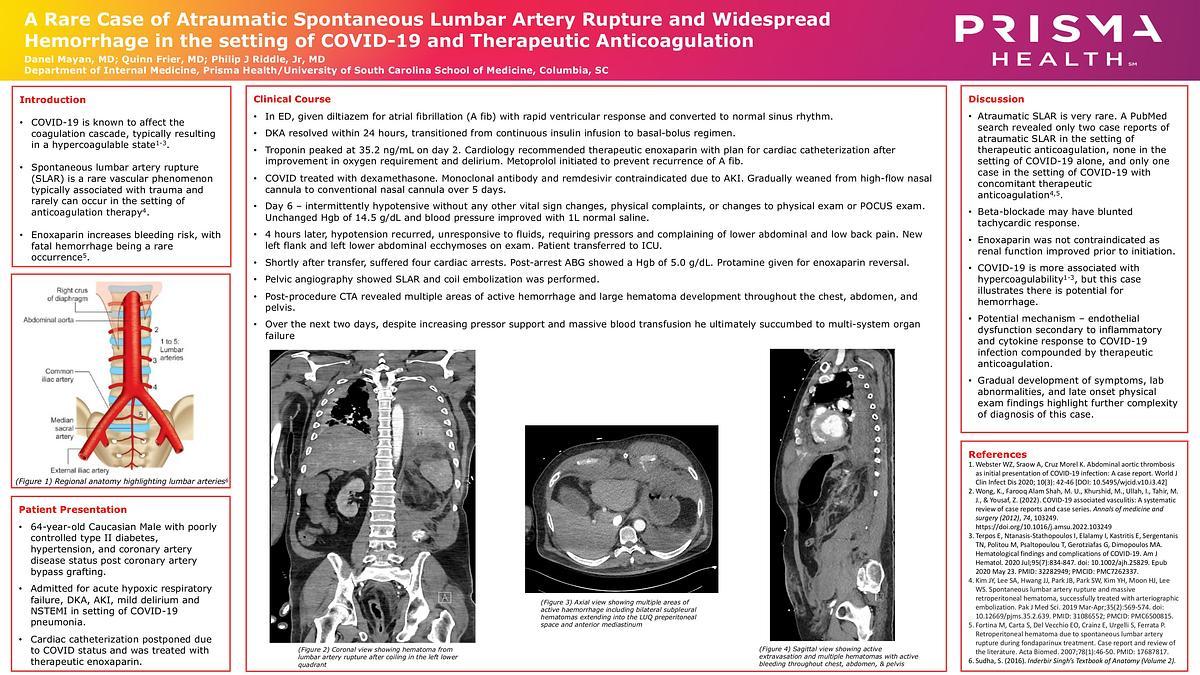

A Rare Case of Atraumatic Spontaneous Lumbar Artery Rupture and Widespread Hemorrhage in the setting of COVID-19 and Therapeutic Anticoagulation